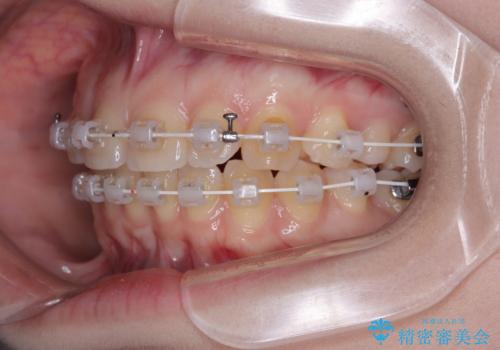

- 審美装置

- 1年4ヶ月

当初はインビザラインを希望されていましたが、職業柄お茶する機会が多く装着時間を確保することが難しいとのことで、相談の上ワイヤー矯正の中では目立ちにくい審美装置で矯正を進めていくこととしました。

1年と少しで矯正治療を終えることができ患者様は大変満足されました。